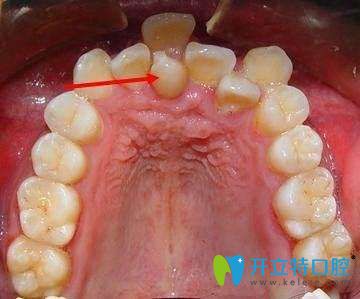

牙齒不齊的圖片

1、影響顧客口腔功能的正常發(fā)揮。降低牙齒的咀嚼效率,還會(huì)導(dǎo)致消化不良及腸胃疾?。灰恍╁e(cuò)合,還會(huì)影響正常的發(fā)音及語言表達(dá);

2、影響牙周組織健康及口腔衛(wèi)生。牙列不齊會(huì)使口腔菌斑易于附著,牙刷也難以接觸,導(dǎo)致牙齦出血、腫脹、口腔異味等癥狀;久而久之還會(huì)累及牙槽骨,出現(xiàn)牙齒松動(dòng)。